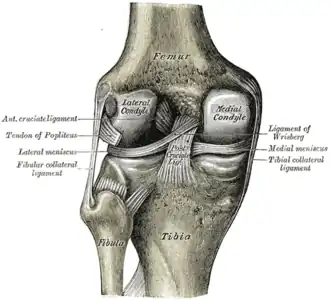

O joelho ainda possui ligamentos que estabilizam a articulação, auxiliados pelos meniscos (interno ou medial e externo ou lateral), que estabilizam o joelho, e amortecem os impactos sobre as cartilagens.

Ligamentos

NomeCápsulaOrigemInserçãoDescrição

ligamento cruzado anterior (LCA)dentrocôndilo lateral do fêmurárea intercondilar anteriorO papel do LCA é prevenir o deslizamento anterior excessivo da tíbia em relação ao fêmur

ligamento cruzado posterior (LCP)dentrocôndilo medial do fêmurárea intercondilar posteriorA lesão deste ligamento é incomum, mas pode ocorrer resultando de uma força de tração traumática do ligamento. Este ligamento previne o deslizamento posterior excessivo da tíbia em relação ao fêmur.

ligamento colateral medial ou ligamento colateral tibial (LCM)foraepicôndilo medial do fêmurcondilo tibial medialO Ligamento Colateral Medial protege a parte medial do joelho de ser aberto por uma força aplicada nas laterais do joelho (joelho valgo).

ligamento colateral lateral ou ligamento colateral fibular (LCL)foraepicôndilo lateral do fêmurcabeça da fíbulao Ligamento Colateral Lateral protege as laterais do joelho de uma força dobrante interior (joelho varo).

Menisco

Os meniscos são elementos cartilaginosos presentes na articulação do joelho que servem para proteger as extremidades dos ossos que se esfregam entre si e para efetivamente aprofundar os soquetes tibiais dentro dos quais o fêmur se prende. Eles também possuem papel na absorção de choque mecânico. Existem dois meniscos em cada joelho, o menisco medial e o menisco lateral. Um deles ou ambos podem ser lesionados, quando o joelho é rodado ou dobrado com força acima do normal, e ou sofre grande impacto.